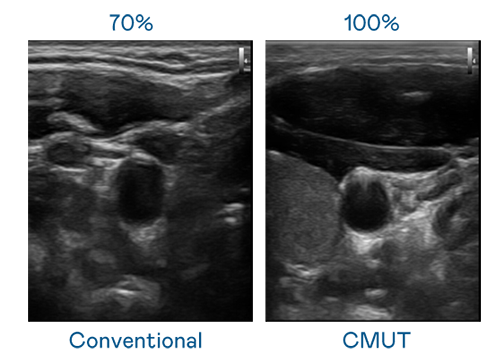

CMUT 技術是一種用電容式微機電元件來產生超音波訊號的技術。與傳統 PZT 壓電式技術相比,CMUT 頻寬增加 30%,更寬頻的超音波訊號讓影像解析度大幅提升,是實現高影像品質醫療超音波掃描、促進精準醫療發展的關鍵技術。

大頻寬帶來超清晰影像

超音波影像的解析度高低,首先取決於探頭能發出的訊號頻寬。尊龙 CMUT 可提供高清晰的超音波訊號,提供高頻寬、高靈敏度、影像紋理細節更高的超音波影像,協助醫護人員縮短影像判讀時間及利用精準的醫療影像進行診斷。